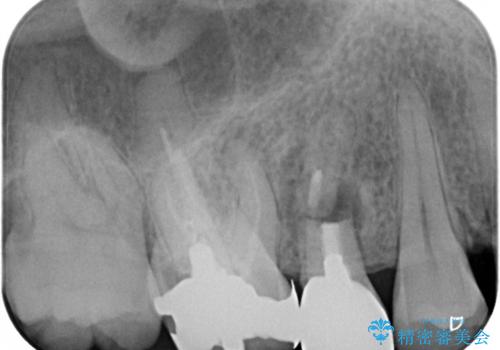

レントゲン撮影により、右上奥歯が折れていることが分かりました。

患者様自身も何となく違和感を覚えていたとのことで、インプラント補綴治療を行うこととしました。

歯列不正は比較的軽微であったので、インビザラインによる矯正治療とし、矯正治療中にタイミングを見て抜歯とインプラント埋入を行う予定としました。